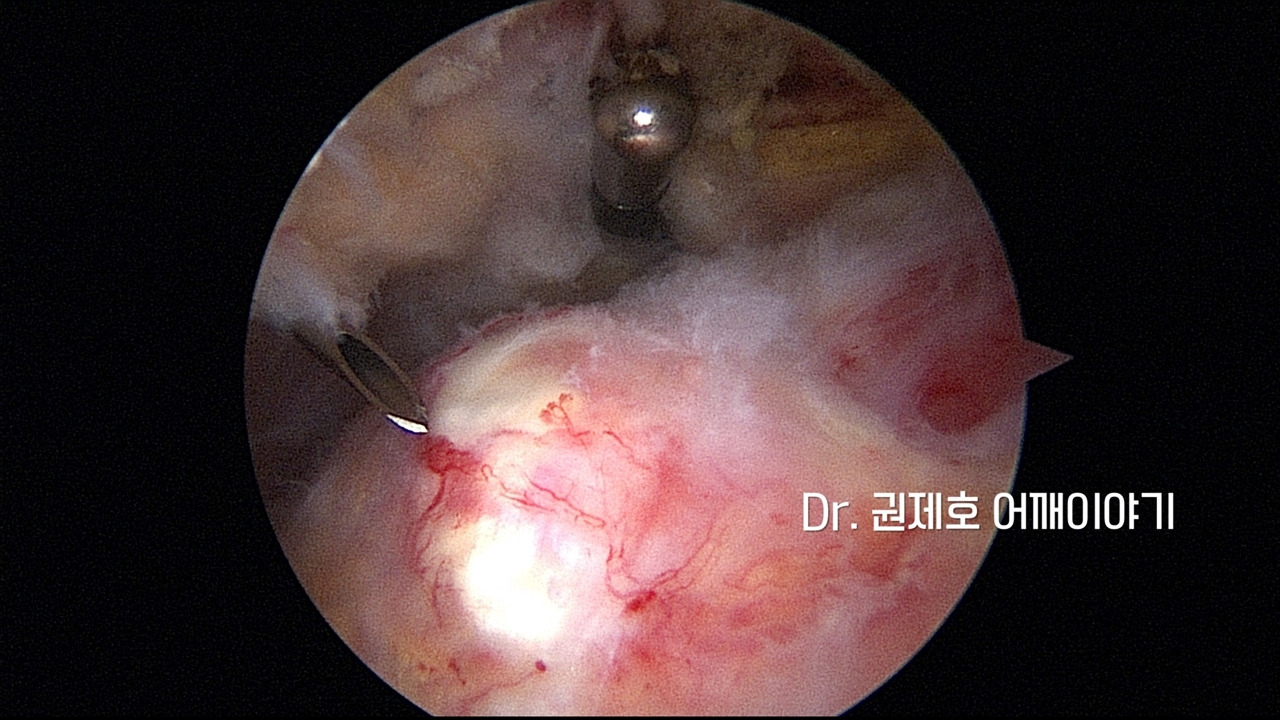

어깨에 생긴 석회성건염의 제거는 관절 내시경을 통해서 한다. 관절경 삽입구 2개를 만들어서 진행한다.

침착된 석회로 인해서 미세혈관즐이 울혈이 되어 있기에 찾기 쉽다. 흰색 덩어리가 인대를 싸고 있는 막안에 존재하는 석회 덩어리이다.

위치를 확인했으니 빠져 나올 수 있게 주사 바늘을 이용하여 구멍을 여러군데 만든다.